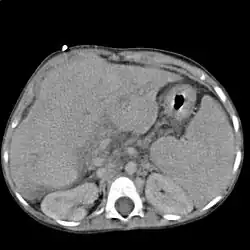

Расширенные и извитые венозные коллатерали выявляются при ангиографии, компьютерной томографии, ультразвуковом исследовании или в ходе оперативного вмешательства.